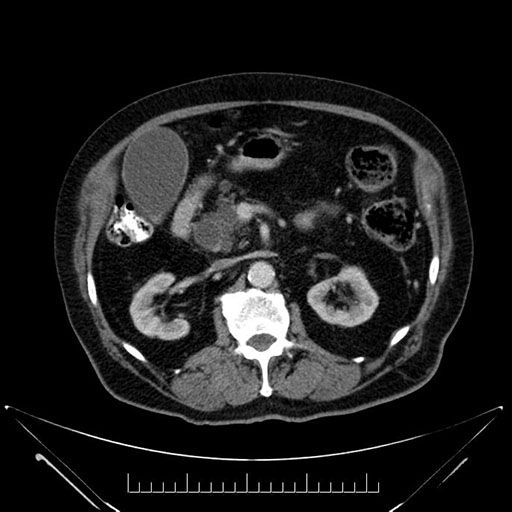

Imaging Analysis

Look through the patient's CT scan to identify any areas of concern for the necessary procedure.

Based on your CT findings, which issue(s) would give reason for "planned slowing down moment(s)" in this case?

Considering a standard Whipple procedure, what step(s) of the operation would you do differently in this case?